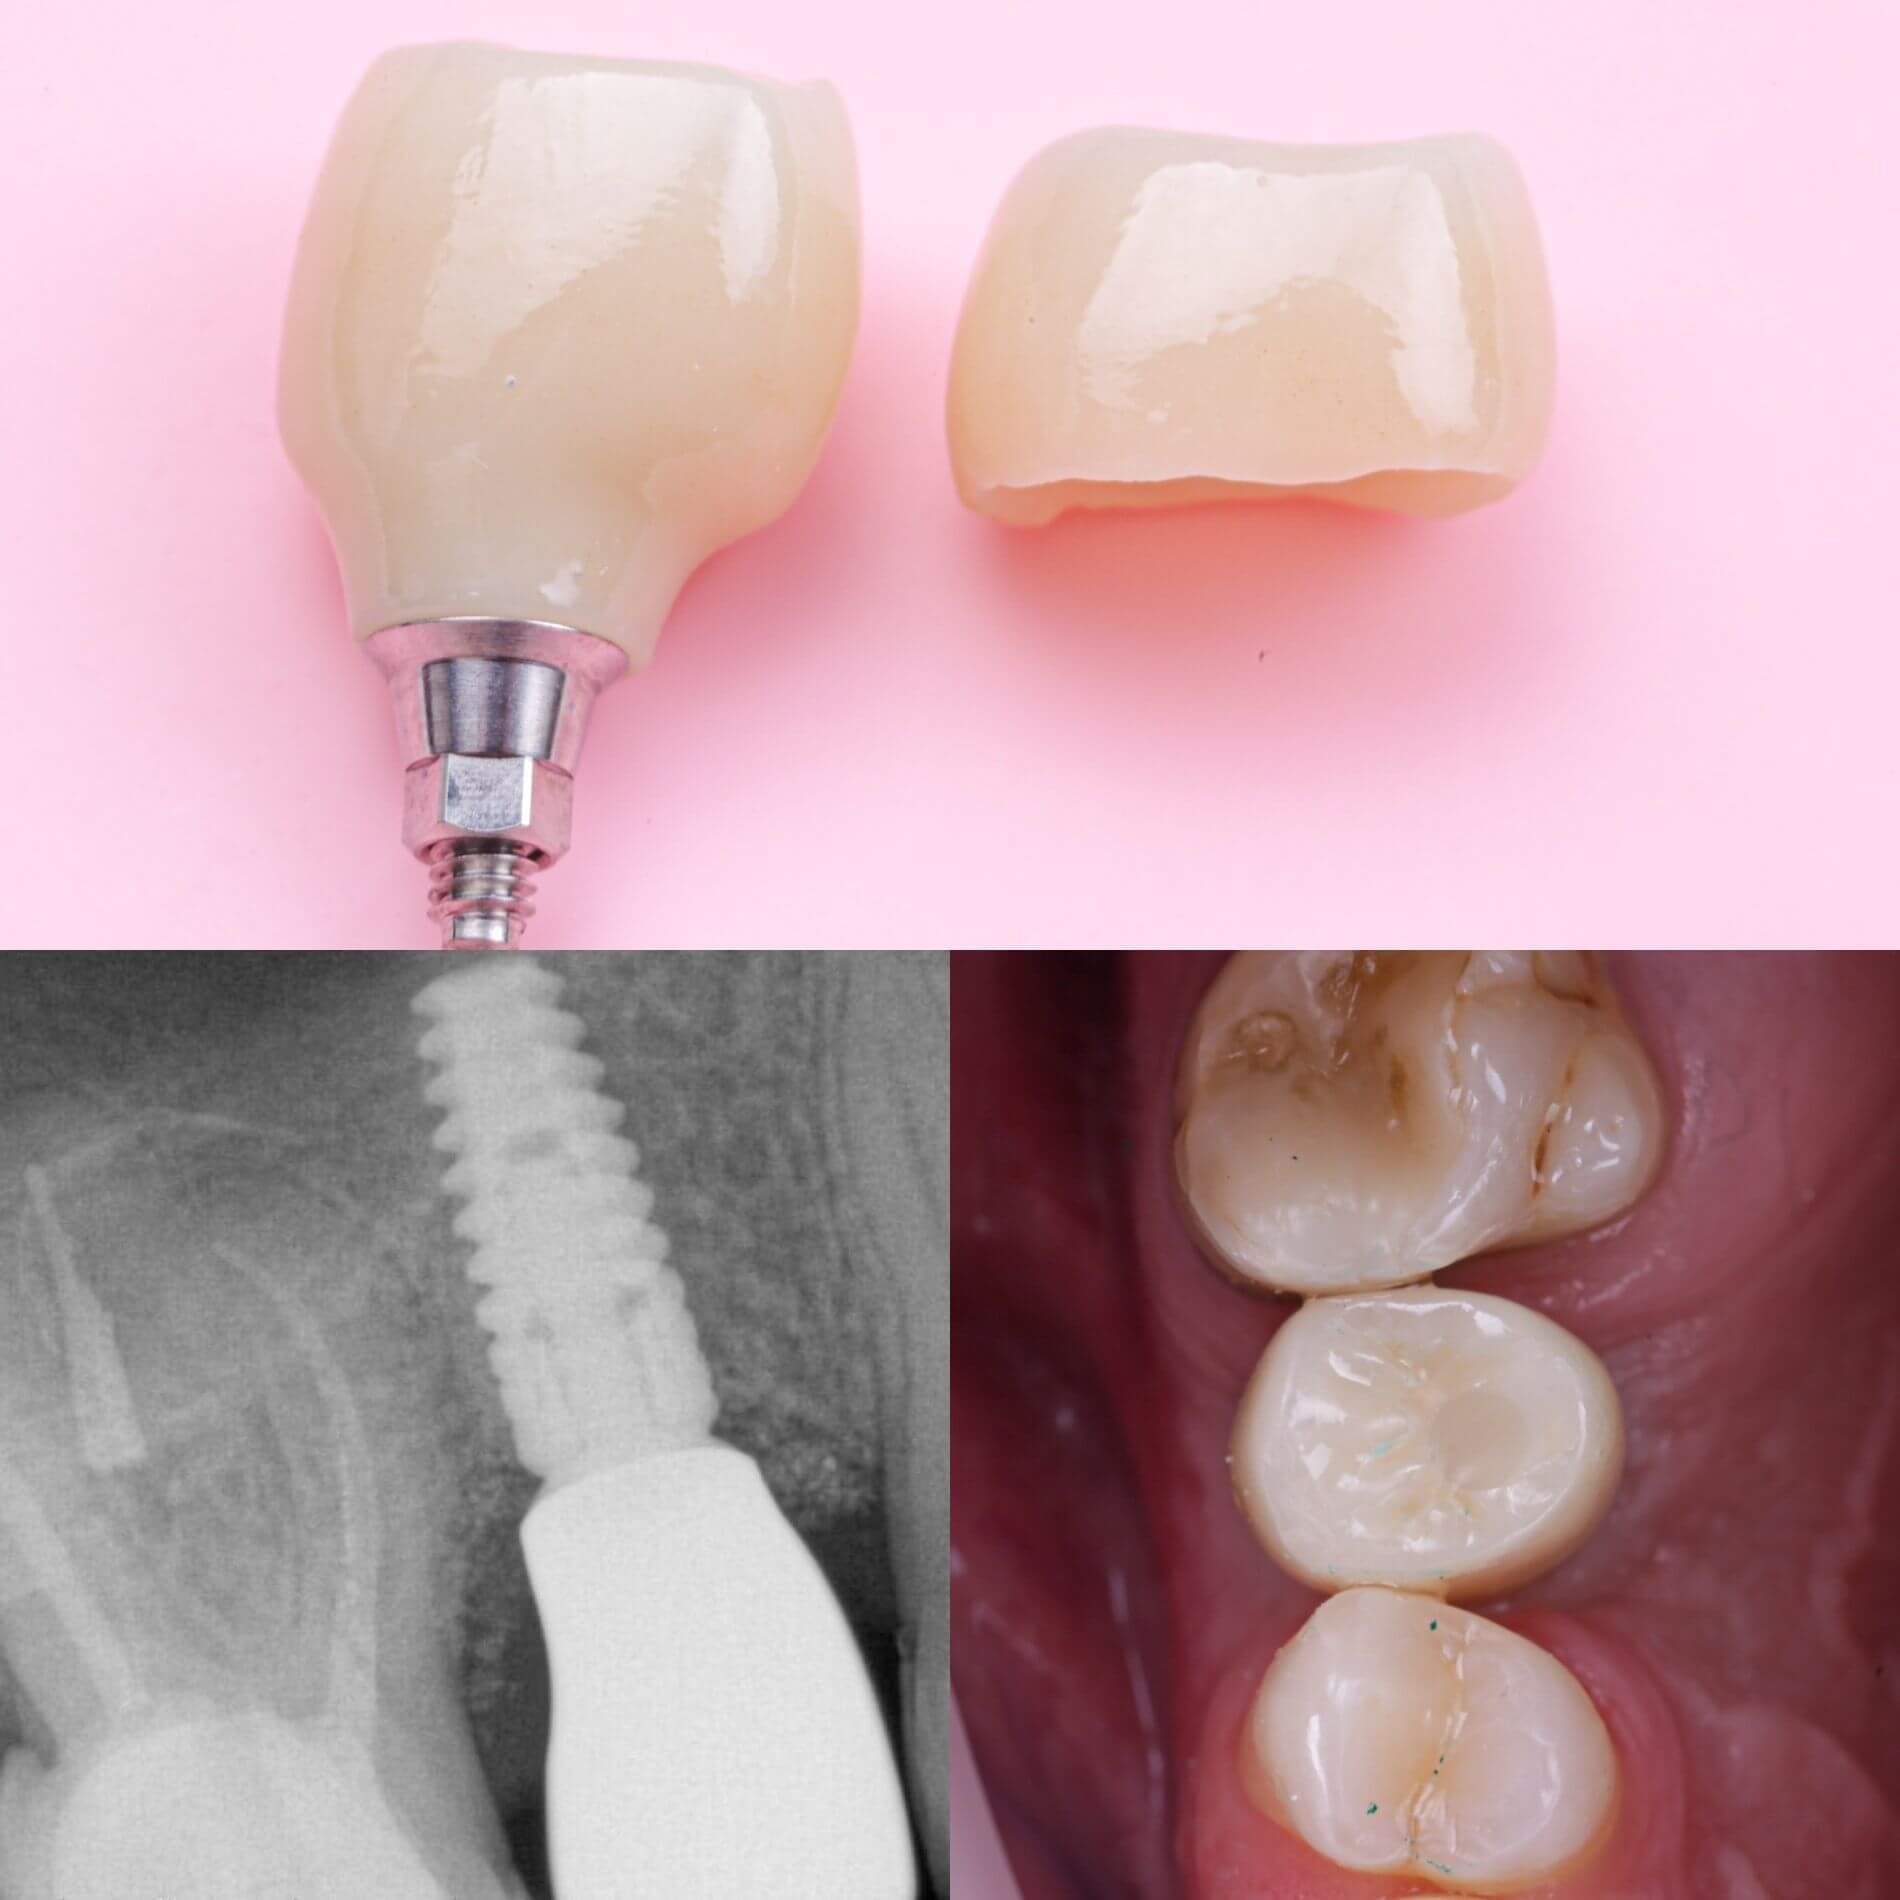

Імплантація - це метод вживлення імплантату (штучного кореня) у верхню або нижню щелепу.Такий штучний корінь виготовляється з спеціального сплаву, що надійно вживлюється в кістку та стає надійною опорою, на яку встановлюється коронка.

- кріплення абатменту та коронки;